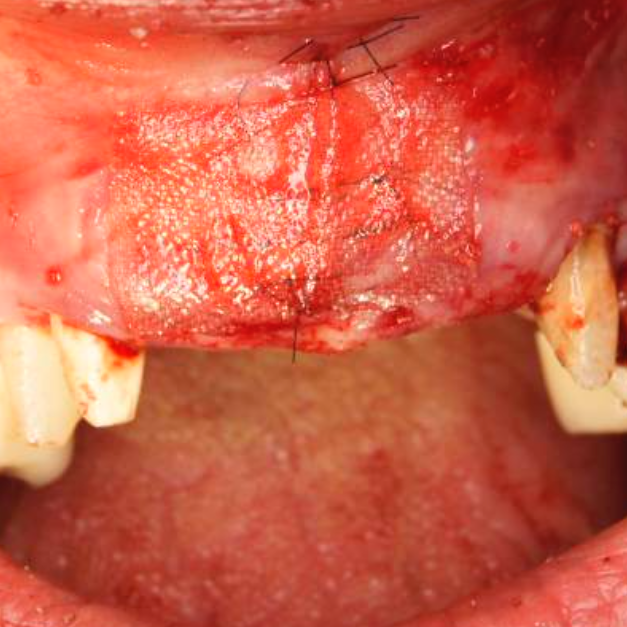

Während oder nach oralen Operationen, von der Extraktion von Zähnen bis hin zu rekonstruktiven Eingriffen, oder Implantationen, bietet BloodSTOP® iX eine schnelle und vorübergehende Kontrolle von Oberflächenblutungen.

BloodSTOP® iX absorbiert schnell Blut und verwandelt sich in ein klares Gel, um die Wunde mit einer transparenten Schutzschicht zu versiegeln, Blutplättchen zu binden und zu aktivieren, sowie die Gerinnung und Wundheilung zu unterstützen.

Anwendungsbeispiele

- Wundversorgung nach Entnahme von Weichgewebstransplantaten

- Parodontale und chirurgische Wunden